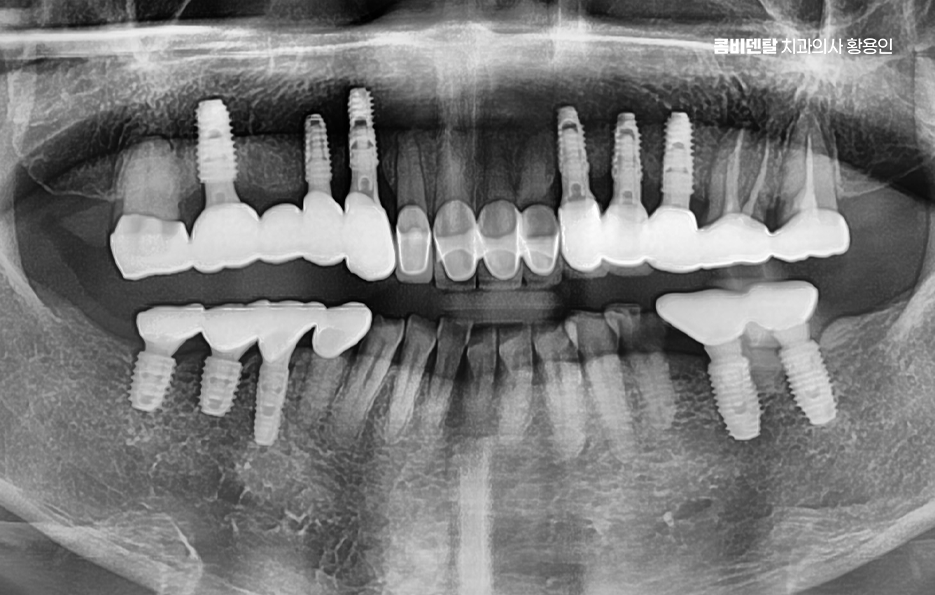

이러한 문제를 막기 위한 효과적인 방법이 바로 임플란트 치료로 어금니 임플란트를 계획할 때는 먼저 잇몸뼈 상태를 정밀하게 확인해야 하며 3D CT 촬영을 통해 뼈의 높이와 두께, 그리고 임플란트를 심을 수 있는 공간을 세밀하게 분석해야 하며 위턱 어금니 같은 경우 상악동이라는 빈 공간이 바로 위에 있어서, 치아가 빠지고 나면 그 공간이 아래로 내려와 임플란트를 심을 자리가 부족해지는 경우가 많고 아래턱 어금니는 하치조신경이라는 중요한 신경이 지나가기 때문에, 신경을 피해서 정확한 위치와 각도로 식립하는 계획이 필요할 수 있어요

결론적으로 어금니 임플란트를 하지 않고 방치하면, 단순히 어금니 하나의 문제가 아니라 전체 교합, 반대편 치아, 나아가 턱관절 기능과 소화 건강까지 영향을 주게 되기 때문에, 가능한 빠르게 치료를 결정하는 것이 장기적으로 더 많은 비용과 시간을 절약하는 방법이 되는 거예요. 특히 뼈가 아직 충분하고, 주변 치아가 건강할 때 임플란트를 진행하면 예후도 좋고, 추가적인 뼈이식이나 부가 수술 없이도 비교적 간단하게 치료가 가능한 경우가 많아서 어금니 상실 후에는 임플란트 치료와의 연계를 잘 고려해서 치료 계획을 늦지 않게 세우시길 바라고 있어요